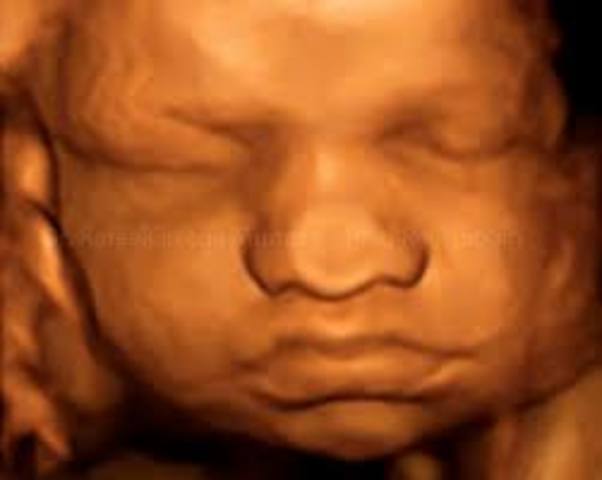

• Semana trigecimo segunda de gestación

Semana trigecimo segunda de gestación

En la semana 32 de embarazo tu bebé y todo su organismo ya están preparándose para lo que será la vida fuera de la placenta que los ha albergado todos estos meses. Medirá unos 47 centímetros y puede que llegue a pesar unos dos kilos.

Los riñones de tu bebé producen orina y sus pulmones comienzan a respirar, su cerebro continúa creciendo y las uñas ya llegan a la punta de sus dedos, por lo que deberás cortárselas al poco tiempo de nacer. Su rostro también es más expresivo y a veces sacará la leng